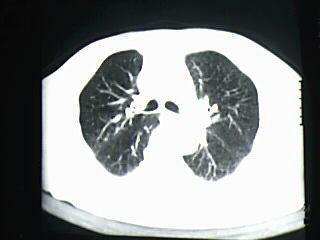

标题: CT19768:男 61岁 胸痛 咯血 一周。无发烧、无结核病史。 [打印本页]

标题: CT19768:男 61岁 胸痛 咯血 一周。无发烧、无结核病史。

右下肺中心型肺癌

右下肺支气管扩张

纵隔窗图像不佳,怀疑右下叶支气管有狭窄,来几张清楚的,暂考虑----感染性病变----抗炎后复查

考虑 右下肺感染性病变,建议抗炎后复查。

考虑右肺下叶感染性病变;建议抗炎治疗后复查。

考虑右肺下叶感染性病变,建议抗炎治疗后复查。

右下肺感染性病变,建议抗炎后复查。支持